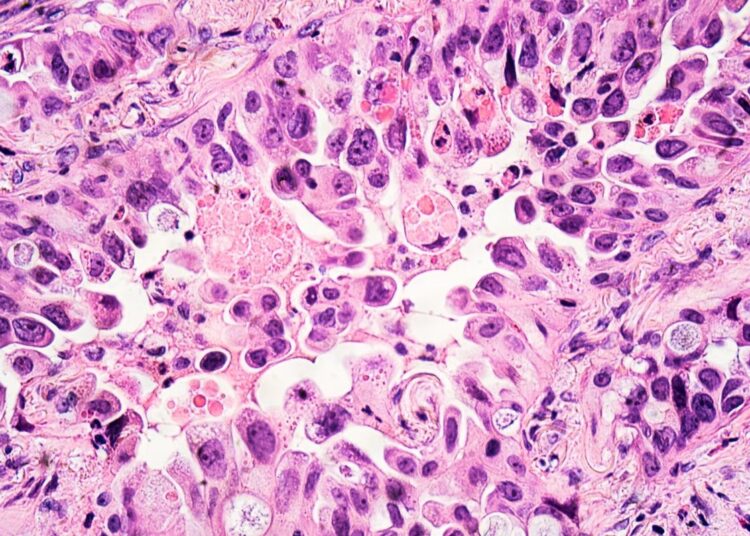

Étude : L’effet du vaccin COVID-19 d’ARNm sur le système respiratoire : cellules humaines de carcinome de poumon au moyen de la spectroscopie et de la représentation de Raman. Crédit d’image : David A Litman/Shutterstock